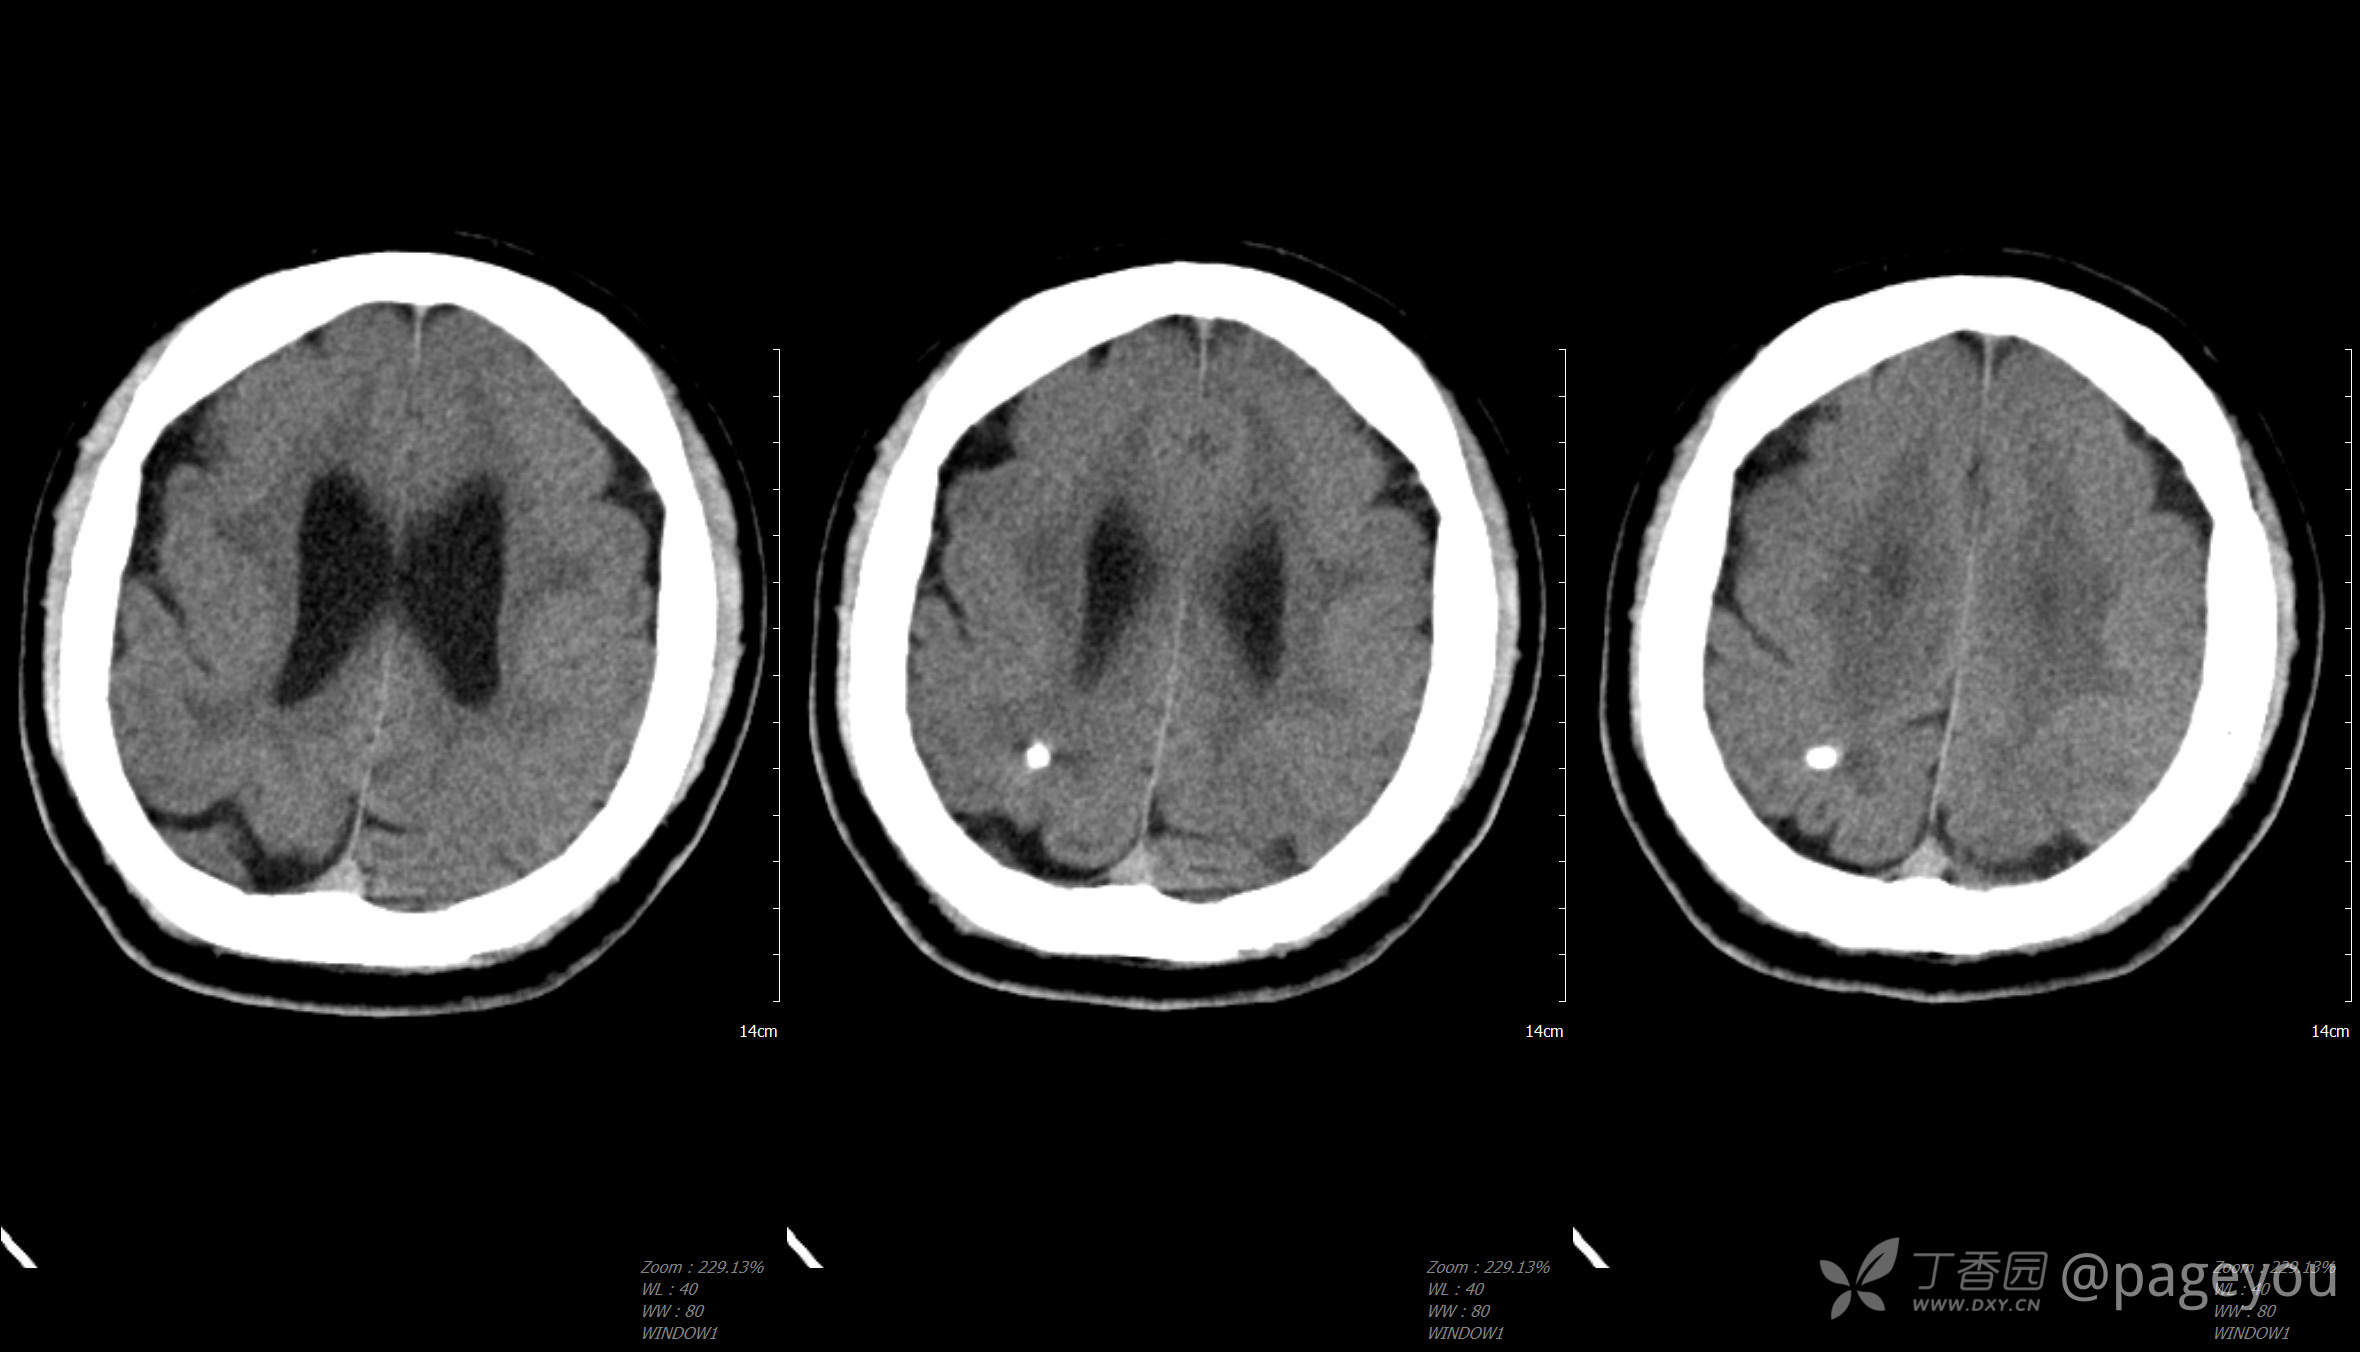

头颅CT: